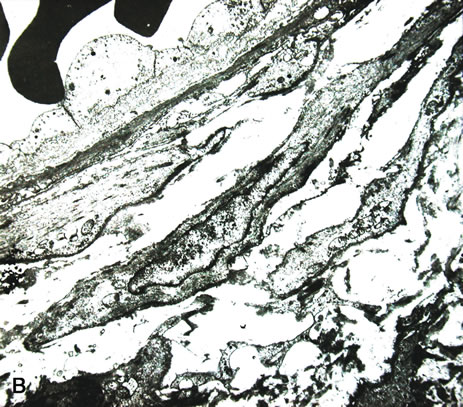

The pars plana and peripheral choroid can be involved with nongranulomatous chronic inflammatory infiltrate. Clinically, such inflammation is seen as vitritis and whitish exudative changes at the pars plana. When it is idiopathic, such inflammatory infiltrate may be termed pars planitis. A moderate to dense vitritis may be present. The vitreous inflammation may clump together and form “snow balls.” Typically, dense white material is present at the pars plana and posterior ciliary body; this is called a “snow bank.” Histologically, enucleated eyes with pars planitis reveal a lymphocytic infiltration in the pars plana and peripheral choroids (Fig. 10). The snow bank is made of fibroglial proliferation containing elements of ciliary epithelium, and vascular channels surrounded by mononuclear cells67–69 Features similar to pars planitis are also observed in patients with multiple sclerosis. Intermediate uveitis without a clear snow bank is seen in patients with sarcoidosis, Lyme disease, and intraocular inflammation associated with human T-cell lymphotropic virus type 1 (HTLV-1) infection.70–73

Fig. 10. Pars planitis. A. Peripheral choroid is infiltrated by lymphocytes. (Hemotoxylin-eosin ×35.) B. The “Snow bank” is made up of fibroglial cells and vascular channels lined by prominent endothelial cells ((×2000).